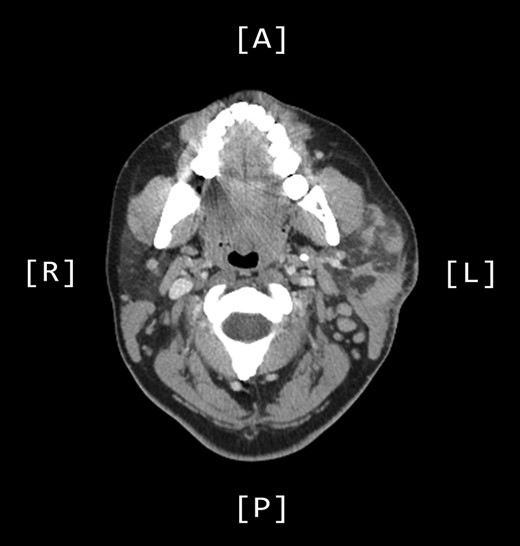

A computed tomography (CT) scan demonstrated left parotid multifocal soft tissue abnormality and enlarged left-sided cervical lymph nodes, with prominent superficial left supraclavicular fossa lymph nodes (Figs 3 and 4).

Axial CT sinuses (with contrast) showing left parotid multifocal soft tissue abnormality and enlarged left-sided cervical lymph nodes.

Coronal CT sinuses (with contrast) showing left parotid multifocal soft tissue abnormality (A) with enlarged left-sided cervical and superficial supraclavicular fossa lymph nodes (B).